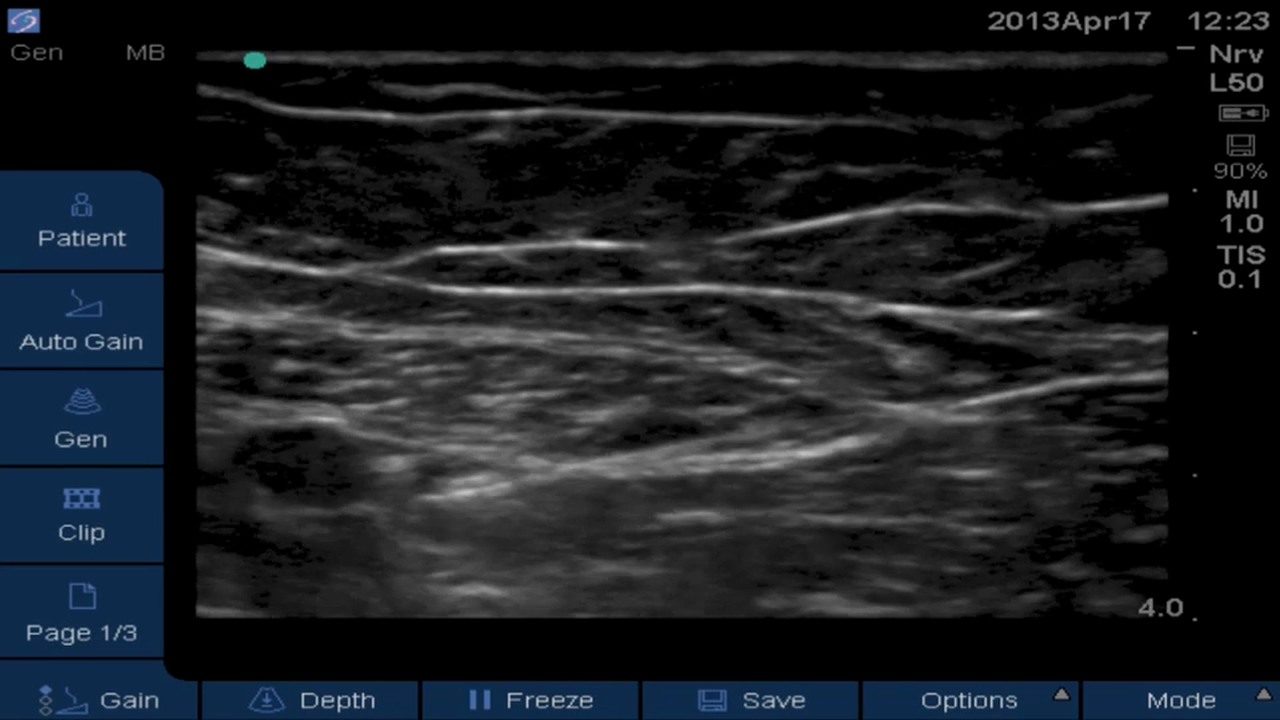

• Saphenous: Adductor Canal Catheter

Block of the Day #6: Brandon Winchester performs a mid-thigh ultrasound-guided saphenous/adductor canal catheter for ACL reconstruction at the Andrews Institute.